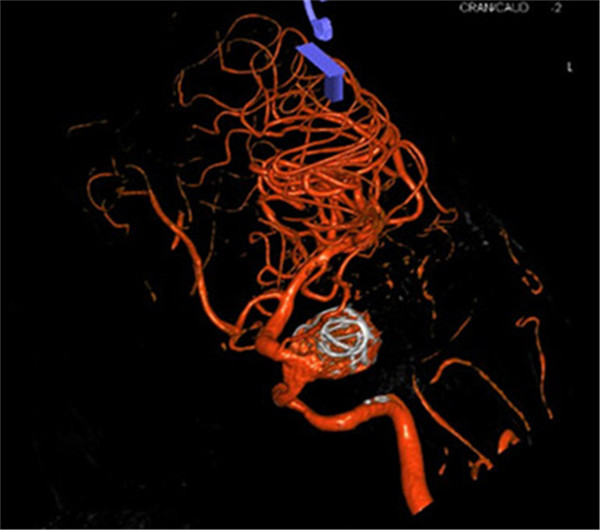

患者是一位70岁的女性,已视物重影1年余,经外院检查确诊为“左侧颈内动脉海绵窦段巨大动脉瘤伴瘤内血栓形成”,医生告知因动脉瘤位于海绵窦内,瘤颈宽约8mm,大小约2.8×2.3×2.2cm,传统手术方法无法完成动脉瘤夹闭或栓塞治疗,同时手术创伤大、风险高。听了医生的话患者不得不放弃手术。

最近,患者因症状加重来到YABO鸭脖第一附属医院求治。该院神经外科张高炼主任主持的治疗团队对该病例进行了讨论和分析,因影像学检查显示动脉瘤载瘤动脉明显迂曲且血管直径较细小,覆膜支架系统通过可能较困难且易引起载瘤血管损伤或动脉瘤破裂出血,他们决定利用密网支架技术行颅内巨大动脉瘤封堵技术为患者治疗。新技术的开展经汇报后得到院领导的大力支持,医院为此简化医疗药械申购手续,购买由美国eV3公司生产的Pipeline血流导向装置(密网支架系统),并邀请到中美合作上海德济医院院长宋冬雷教授前来会诊和指导。

手术在气管插管全麻下进行,微导管顺利送到理想位置,由于出现血管痉挛,立即行解痉处理,好转后置入血流导向装置,由于瘤腔血流速度快,置入弹簧圈支撑支架,并缓慢释放装置,经造影显示动脉瘤消失,载瘤动脉通畅。手术过程顺利,术后患者神志清醒,言语切题,视力无异常改变,四肢活动正常,患者已缓慢下床活动,手术获得圆满成功。手术当日有来自广西区内多家医院神经外科主任的现场观摩与交流。

术前CTA

密网支架置入